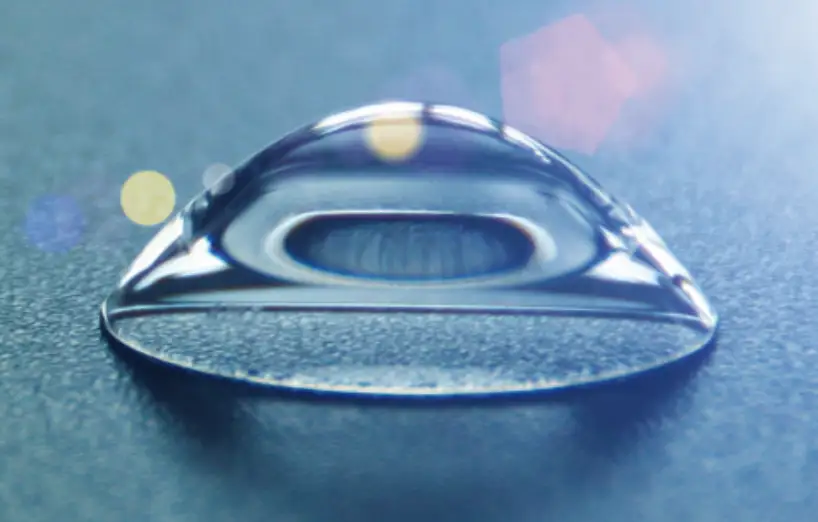

Lentes RPG o Esclerales

Adaptadas a córneas poco convencionales, con diseños de última generación.

Orto-K

Lentes que corrigen la visión mientras duermes.

Las lentes Orto-K, también conocidas como “lentes pijama”, moldean suavemente la superficie corneal durante la noche, permitiendo al paciente prescindir de gafas o lentes de contacto durante el día.